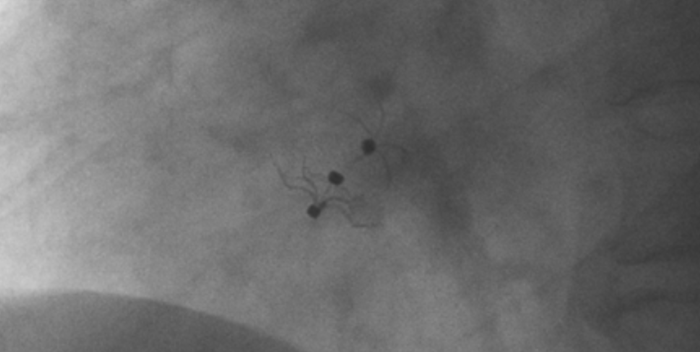

術(shù)中造影顯示患者為PFO且長(zhǎng)隧道型,目前市場(chǎng)上已商業(yè)化的PFO封堵器難以滿足該患者解剖結(jié)構(gòu)封堵需求。迪創(chuàng)醫(yī)療自主研發(fā)的OmniSeal PFO封堵器自適應(yīng)性雙盤貼合設(shè)計(jì)能廣泛適應(yīng)不同PFO隧道長(zhǎng)度的解剖結(jié)構(gòu)和形態(tài),其雙盤外包覆式阻流和隧道內(nèi)填充阻流相結(jié)合的雙重阻流設(shè)計(jì),可為此患者實(shí)現(xiàn)有效封堵。與此同時(shí),OmniSeal首創(chuàng)的完全可穿刺式設(shè)計(jì),也為此患者最大程度地保留了房間隔區(qū)域穿刺通道,以實(shí)現(xiàn)全兼容未來可能的左心系統(tǒng)二次介入術(shù)。術(shù)終造影和心臟超聲顯示封堵完全、效果良好。作為OmniSeal的首例臨床應(yīng)用,本次手術(shù)的順利完成和優(yōu)異效果充分體現(xiàn)了產(chǎn)品的設(shè)計(jì)創(chuàng)新優(yōu)勢(shì)。

影像顯示試驗(yàn)器械適應(yīng)性貼合于房間隔兩側(cè)且穩(wěn)定